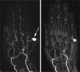

Posttraumatic pseudoaneurysm

Traumatic aortic rupture, also called traumatic aortic disruption or transection, is a condition in which the aorta, the largest artery in the body, is torn or ruptured as a result of trauma to the body. The condition is frequently fatal due to the profuse bleeding that results from the rupture. [Source: Wikipedia ]